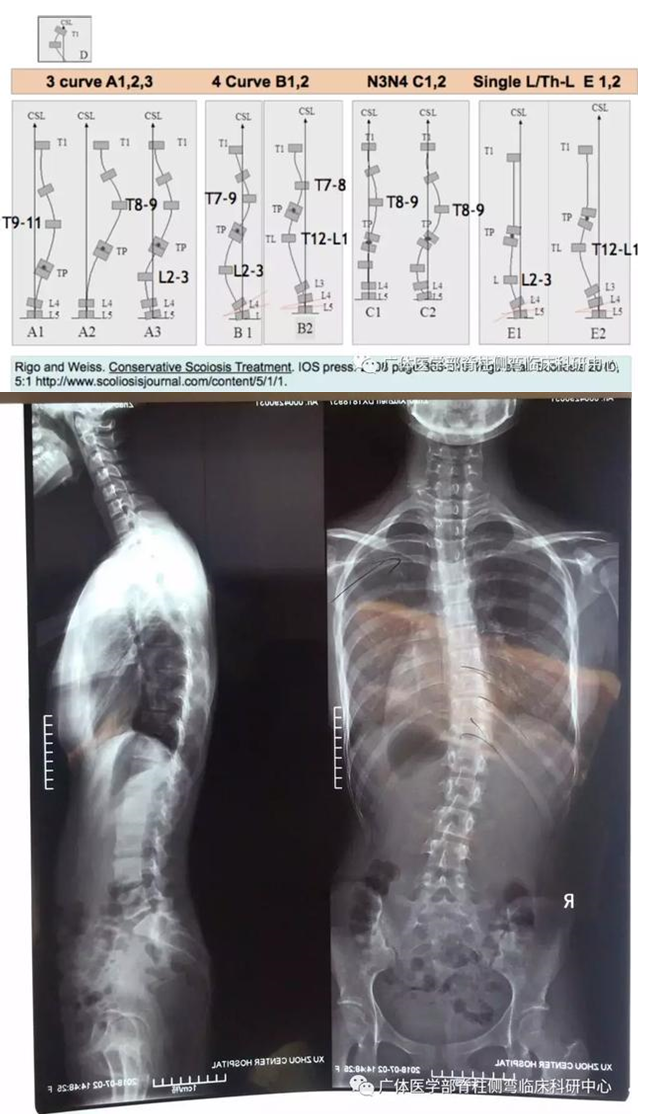

图3︰X片所示:RigoA1型,T5-L3右凸Cobb26°

图6︰X片所示:RigoB1型,T4-T10右凸Cobb22°,T10-L4左凸Cobb42°

图9︰X片所示:RigoB1型(伴近胸弯),T1-T4左凸Cobb30°,T5-T11右凸Cobb29°;T11-L3左凸28°